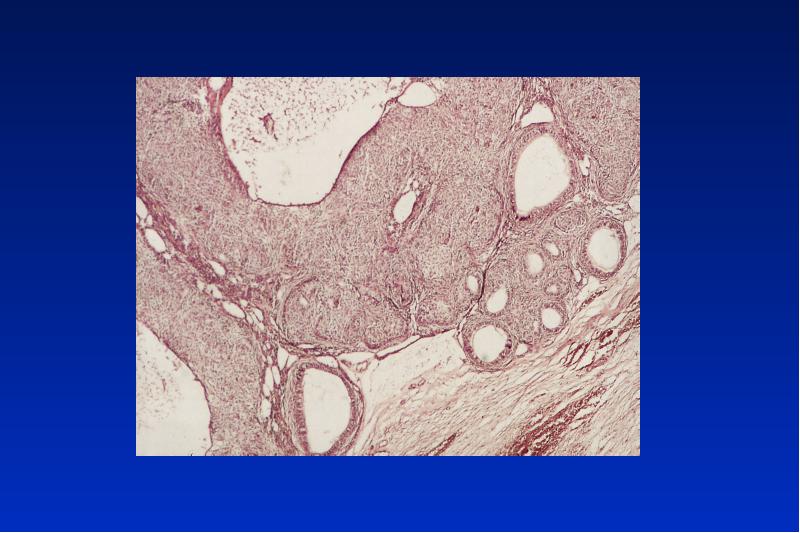

- 21. Odontogene Keratozyste Lok: UK Alter: 20 - 30, 50 - 60

- 23. Gorlin-Goltz Syndrom autosomal dominanter Erbgang Symptome: multiple